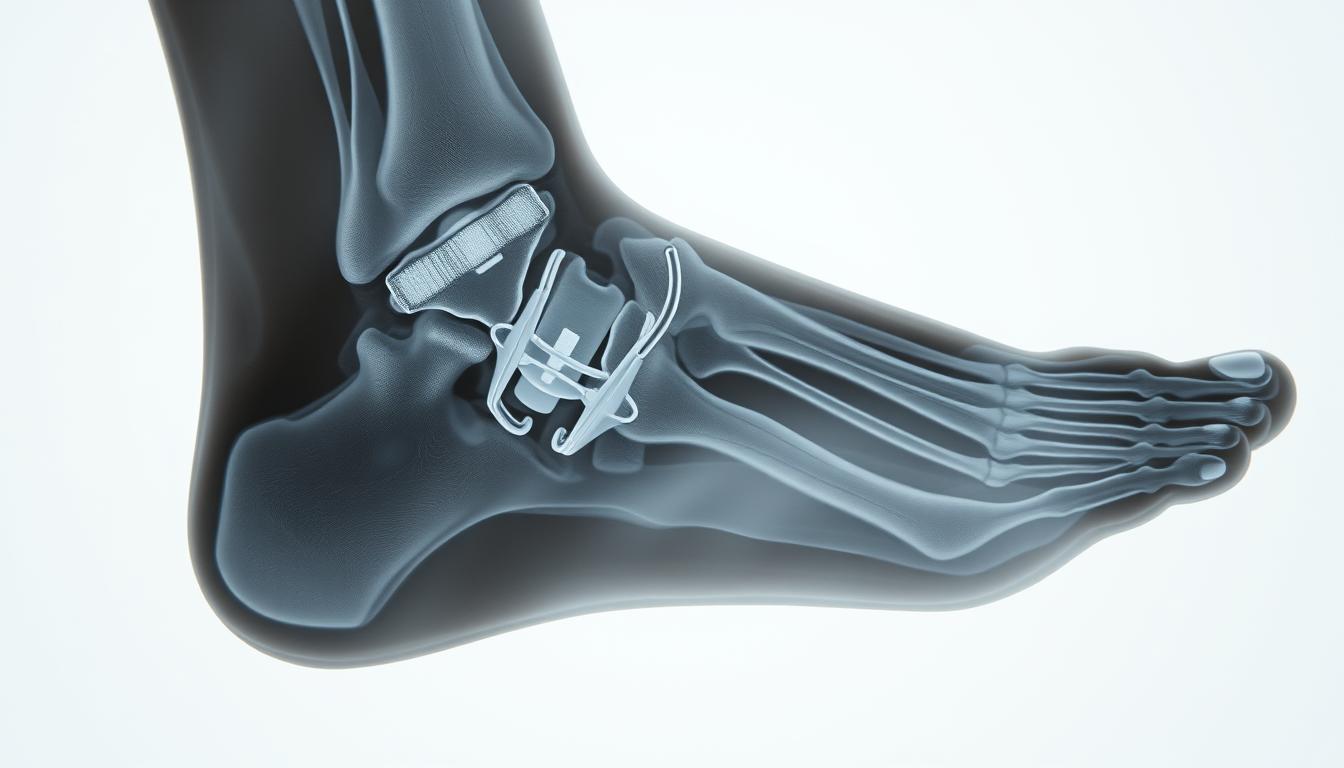

Co tak naprawdę dzieje się w naszym ciele, gdy mówimy o zroście kości po operacji haluksa? Choć proces ten może wydawać się skomplikowany, jego zrozumienie jest.

Rehabilitacja po operacji haluksa jest kluczowym aspektem, który wpływa na proces odzyskiwania pełni…